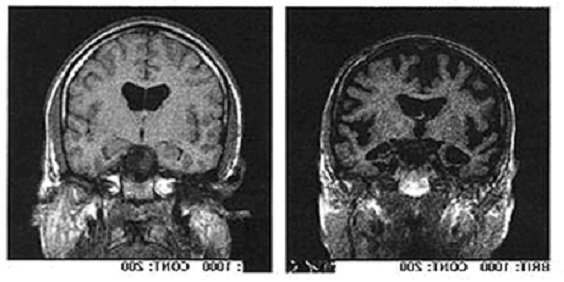

Il cervello di un individuo affetto da Alzheimer appare come un pallone sgonfio a causa della continua eliminazione di neuroni. A sinistra c'è un cervello sano, a destra uno malato.

È assolutamente evidente dalle foto precedenti quanto sia dannoso ed ingente il danno che l'Alzheimer reca al tessuto nervoso: il cervello si sgretola, perde di consistenza accartocciandosi su se stesso. Fu proprio questa la visione che portò il dottor Alzheimer a descrivere il cervello malato dicendo che «presentava una scarsità di cellule nella corteccia cerebrale». Inoltre, le cellule rimaste vengono saturate di placche senili di β-amiloide, rendendo complicati i trasferimenti degli impulsi da una parte all'altra del sistema nervoso. Queste placche sono quelle che Alzheimer definì nell'autopsia di Auguste come «gruppi di filamenti localizzati fra le cellule nervose».